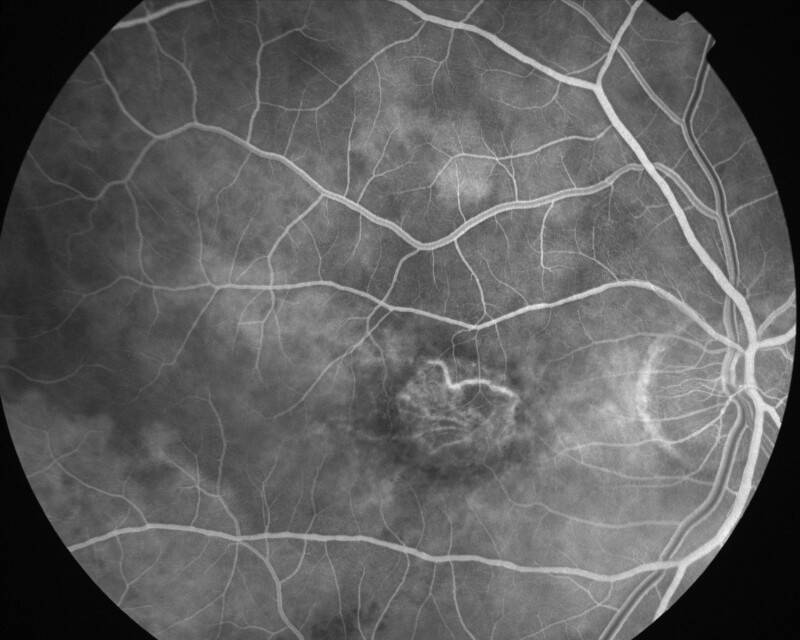

ATROPHIE AREOLAIRE CENTRALE

IMG0006.jpg